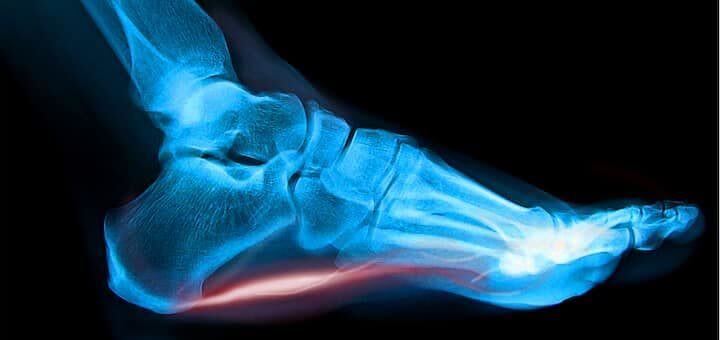

It is the most commonly occurring cause of heel pain, involving a band of tissue in the foot called the plantar fascia that connects your heel bone to your toes. It's job - to help support the arch in your foot during your normal walking and running gait. Injury to this tissue can occur for a wide variety of reasons but usually affects the area just in front of the heel bone. And the pain can be the most sore in the morning, after rest or when pressed directly. During the early stages, plantar fasciitis pain tends to ease off with activity, but as time goes on the pain may not subside entirely.

There are thought to be a few possible causes of plantar fasciitis. The most widely recognised is by mechanical stress either by abnormal motion of the heel itself, excessive load/impact or by a traction injury where the plantar fascia is being pulled too much. The second is due to the development of heel spurs causing fibrosis and calcification and weakness in the plantar fascia and the final possible cause is by an inflammatory joint disease like arthritis.